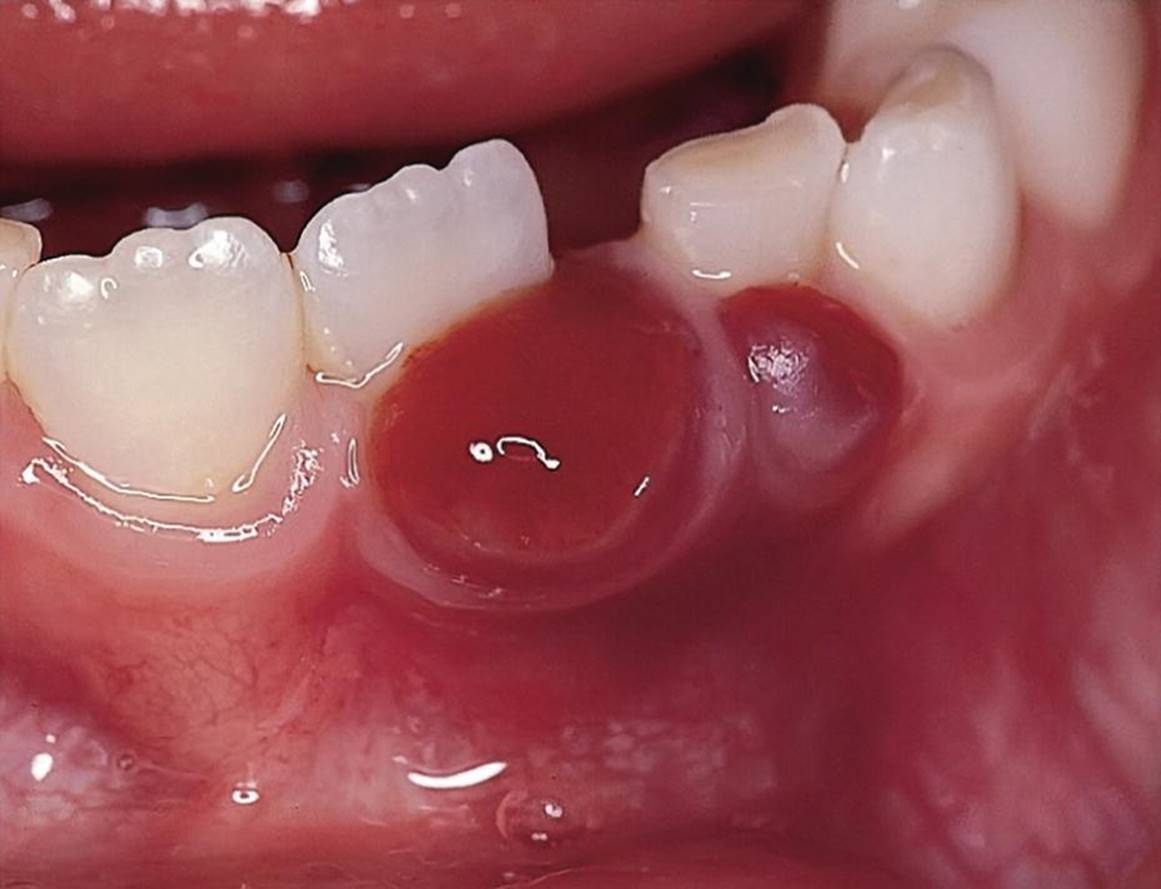

Epulides are by definition tumor‐like hypertrophic tissue formations located on the gingival mucosa. The etiology is often trauma or irritation in connection with tooth eruption or exfoliation. The size may vary from some millimeters up to several centimeters in diameter. They differ in surface texture, consistence and color, depending on the tissue composition. Pyogenic granuloma, peripheral calcifying granuloma, and peripheral giant cell granuloma (Figures 15.19, 15.20 and 15.21) are all examples of epulides. The treatment is excision, and the final diagnosis is confirmed by histopathologic analysis.

Figure 15.21 Peripheral giant cell granuloma.